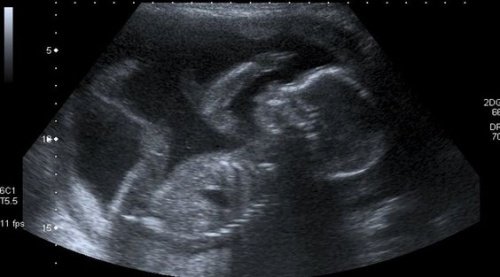

Een vrouw weet dat ze een moeder is tijdens de eerste echografie. Ze kan onmogelijk haar tranen tegenhouden bij het horen van de snelle hartslag van haar kind. Haar hart slaat al even snel, helemaal overweldigt door blijdschap door het eerste contact met haar ongeboren baby.

Tijdens de komende negen maanden zal ze het moeten doen met de wazige echo’s op een zwart-wit schermpje voordat ze oog in oog komt te staan met haar zoon of dochter. Voordat ze de kleur van haar huid, haar en ogen zal kennen.